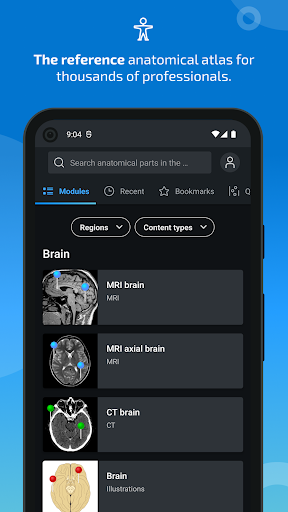

*Find your anatomical parts more easily thanks to the new, more intuitive and powerful search feature

New : You can now filter the modules by region or by content type so you can find the module you are looking for much faster.